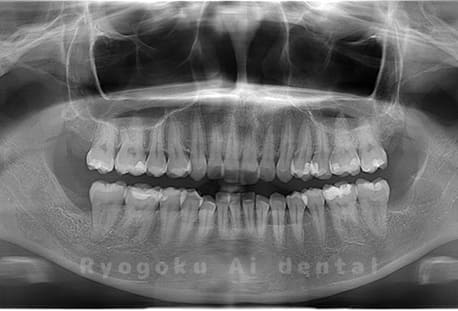

Case03

- 原因

- 上顎、下顎の親知らず

- 治療内容

- 上下4本の親知らずを抜歯したケースです。

<リスク・副作用>

手術後は痛み、腫れ、痺れなどの副作用が生じる場合があります。